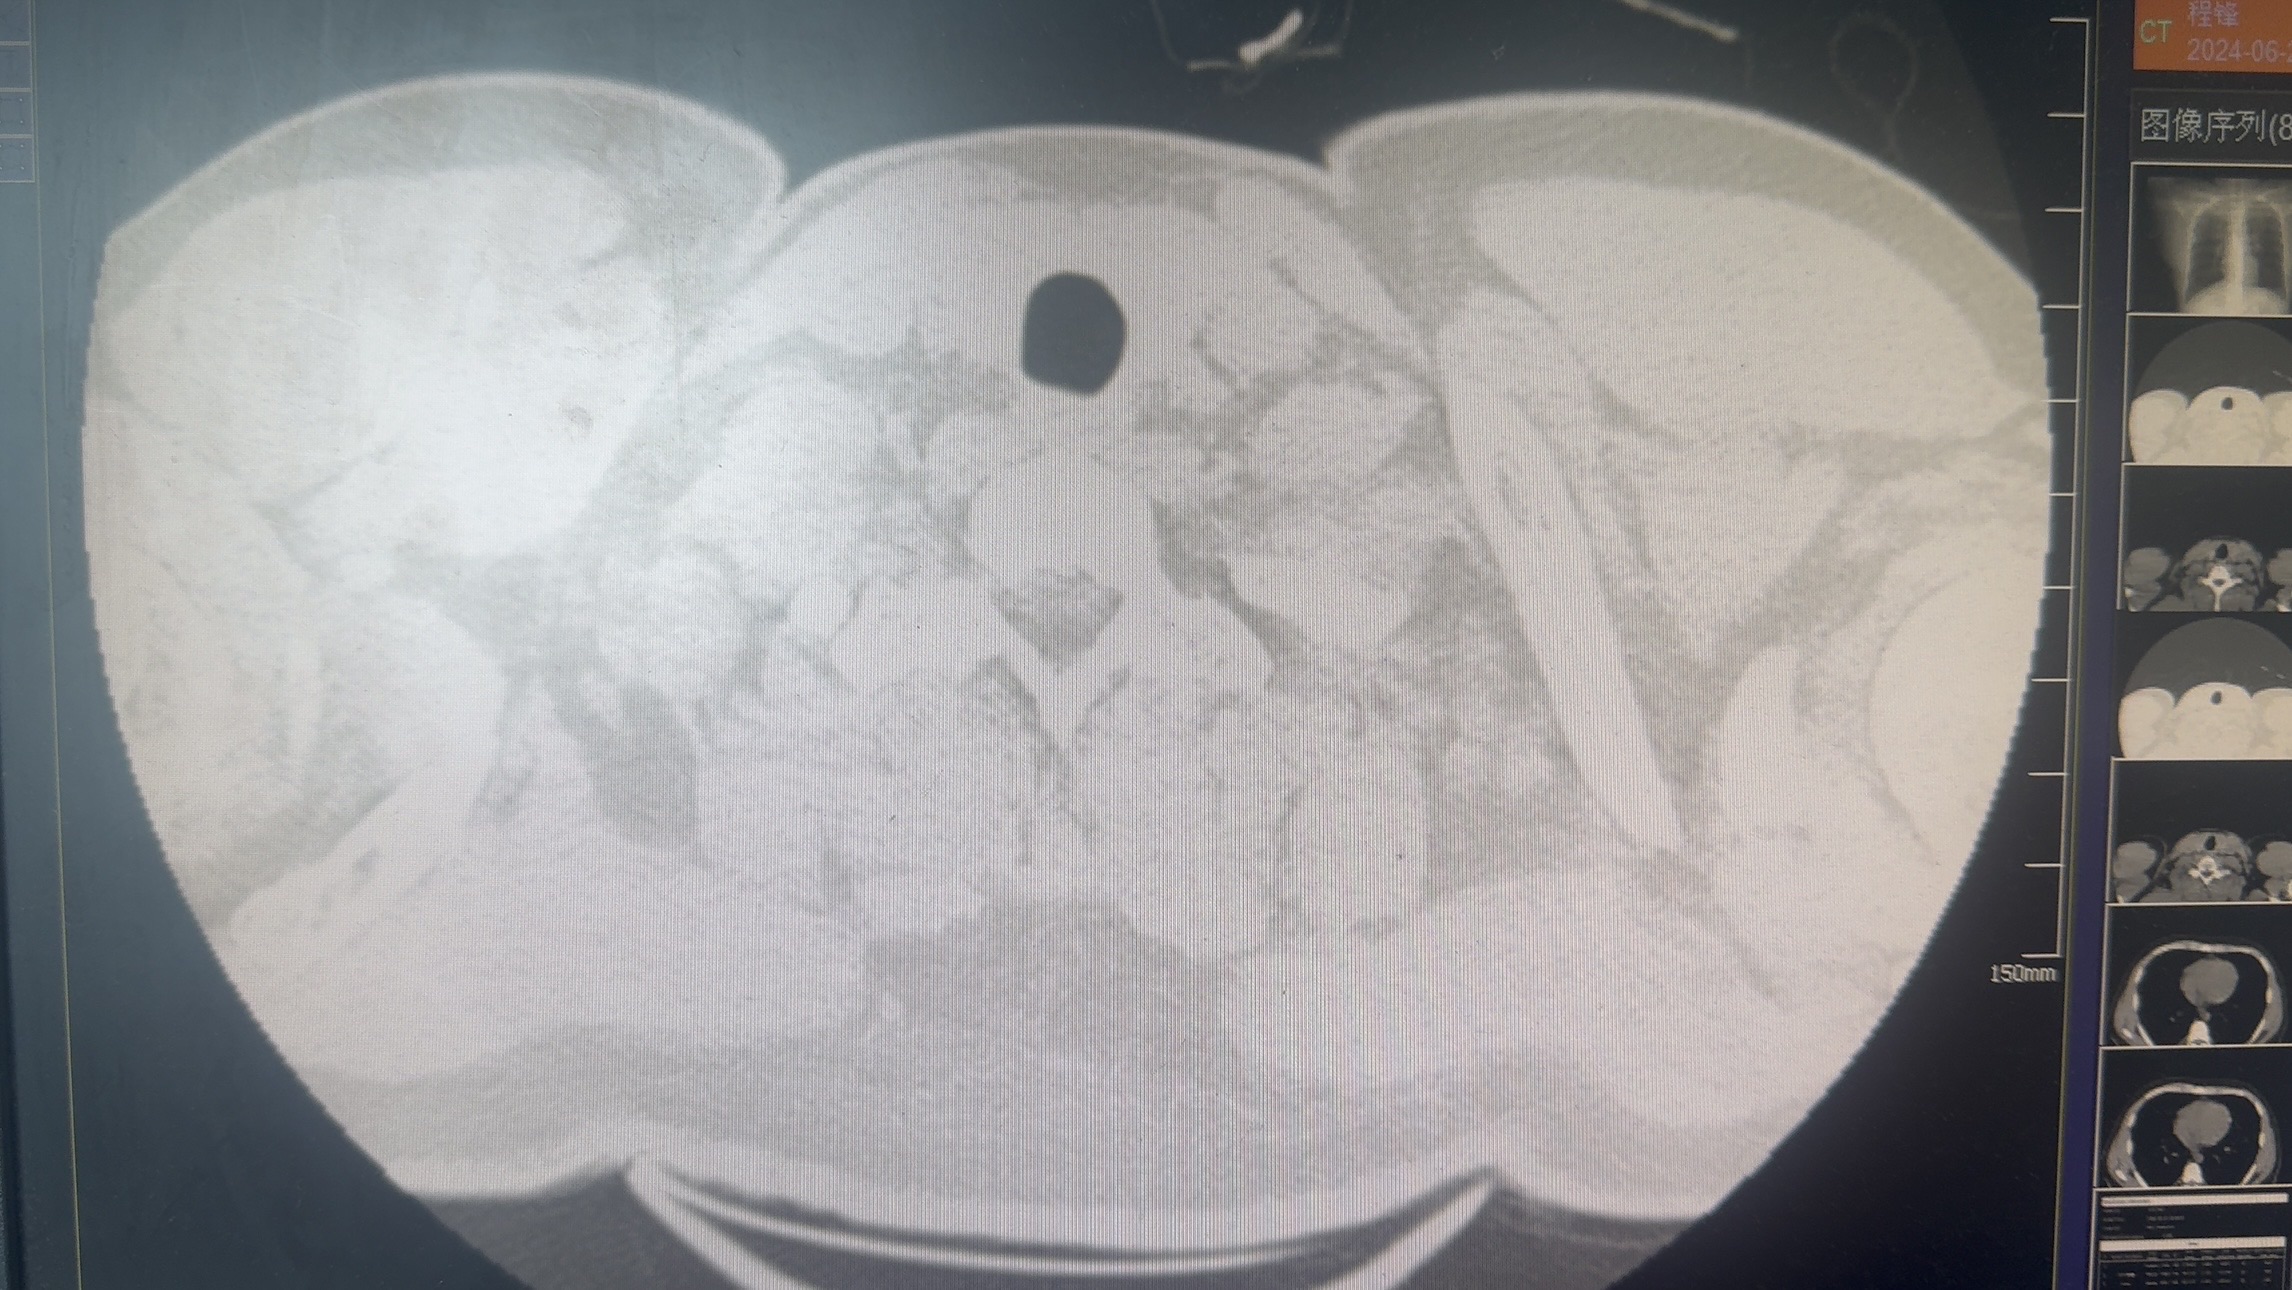

于6.26-7.3应用利奈唑胺600mg q12h,6.29-7.3头孢唑林2.0g q8h,体温未控制,仍每日出现发热,体温最高39度,遂停用利奈唑胺,7.4改用万古霉素1.0g q8h。用药3天后体温控制,患者7.9自动出院。出院第二天再次出现发热,体温40度。患者于6.29诉胸痛,复查ct

7.9复查ct示

7.12再次入院,继续给予万古霉素及头孢唑林治疗,7.17再次出现发热,7.17-7.22每日均出现发热,体温最高40度。7.18复查ct